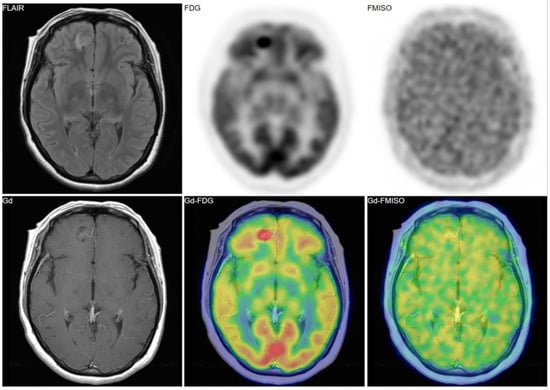

Figure 2, Figure 3 and Figure 4 show some representative cases of low to high grade gliomas. We demonstrated that FMISO has the potential to distinguish glioblastomas (i.e., grade IV gliomas) from less-malignant gliomas (i.e., grade III or lower grade gliomas) [40]. As mentioned above, the oxygen concentration threshold of FMISO uptake is low. Thus, FMISO PET can differentiate tissues with severe hypoxia from those without. Studies using direct needle electrodes suggested that the hypoxic condition of a glioma depends on its degree of malignancy [41,42,43]. We used FMISO PET and FDG PET for the preoperative examination of 23 patients with gliomas of different World Health Organization (WHO) grades [40]. The PET findings were compared with the patients’ post-operative histological findings by neuropathologists. We observed FMISO uptake in the glioblastomas, but not in the less-malignant gliomas (Table 1). In the WHO definition, glioblastoma presents with necrosis in the tumor, whereas lower-grade gliomas do not develop necrosis [44]. It is thus reasonable that only glioblastomas have severe hypoxia (beyond the FMISO threshold) and therefore take up FMISO. We concluded that FMISO PET may be able to clearly distinguish glioblastomas from lower-grade gliomas.

Figure 3. A 38-year-old patient had a tumor in the right frontal lobe. FMISO uptake was absent despite of strong uptake of FDG. The pathological diagnosis was gangliocytoma (grade I).